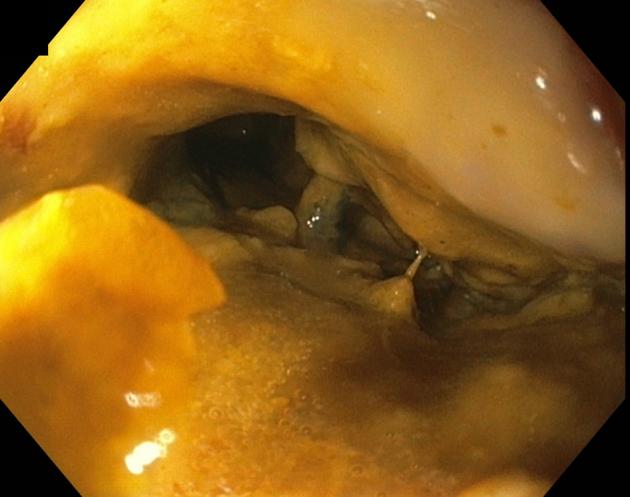

In this video case series, 3 cases of CVF patients treated endoscopically are presented to demonstrate the use of the currently available tools and techniques. The strategy used for the closure of the 3 CVFs was dependent on the size and etiology of the fistulas.

These cases demonstrate the use of the cap to perform vaginal endoscopy; the use of the over-the-scope clips, covered stents, and endoscopic suturing; and how they can facilitate the closure of fistulas in patients who are poor surgical candidates.